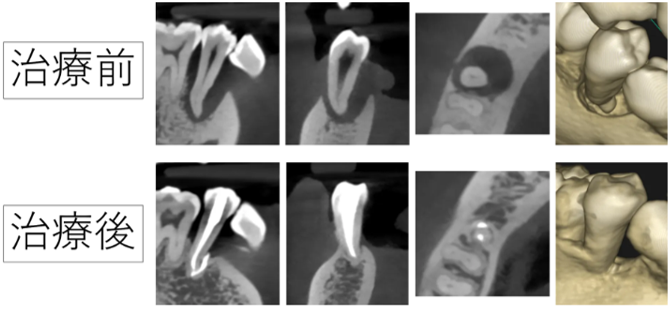

【症例】神経を抜く治療を失敗。大きく骨が溶けた奥歯の再根管治療